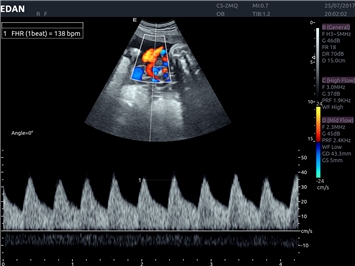

• Кардиологических исследований

Тканевой допплер:

Да

Постоянно-волновой допплер:

Импульсно-волновой допплер:

Триплексное сканирование: